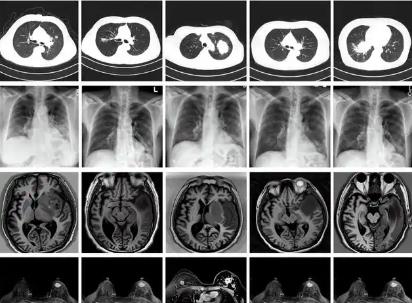

我國科學家建立生成式模型為醫學AI訓練提供技術支持

北京大學與溫州醫科大學的研究團隊建立一種生成式多模態跨器官醫學影像基礎模型(MINIM),可基于文本指令以及多器官的多種成像方式,合成海量的高質量醫學影像數據,為醫學影像大模型的訓練、精準醫療及個性化診療等提供有力...